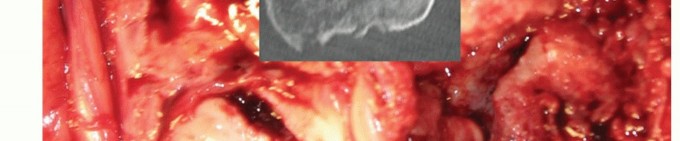

During a distal humeral hemiarthroplasty (DHH), the bony preparation is focused on the medial and lateral columns. When these are not intact, reconstruction with temporary K-wire fixation to judge length and more definitively either wire or tension band fixation or plate and screw fixation should be attempted (TECH FIG 4I-N). The preservation and reconstruction of the columns are especially important when using an implant without an anterior flange.

TECH FIG 4 • (continued) I-K. Latitude DHH. I. Intact medial and lateral humeral columns, with a red vessel loop loosely around the ulna nerve. J. AP radiograph demonstrating the trochlea and capitellum correctly sized for the host, greater sigmoid notch of the ulna, and the radial head. K. Lateral radiograph demonstrating a well-aligned radio capitellar joint and osseous integration of the anterior flange. L-N. Sorbie DHH. L. Fractured medial and lateral columns were reconstructed with K-wires, prior to implant insertion. M. AP radiograph demonstrating a well-seated Sorbie implant with healed medial and lateral columns. N. Lateral radiograph demonstrating a well-aligned radiocapitellar joint with posterior heterotopic ossification in the traumatically injured triceps muscle.